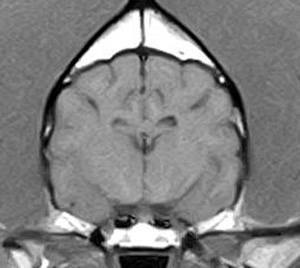

けいれん発作が出るワンちゃんが来院されました。MRI検査では脳に構造上の異常を認めず、特発性てんかんとの診断でお薬での治療となりました。発作は現在のところ、お薬で良好にコントロールされています。